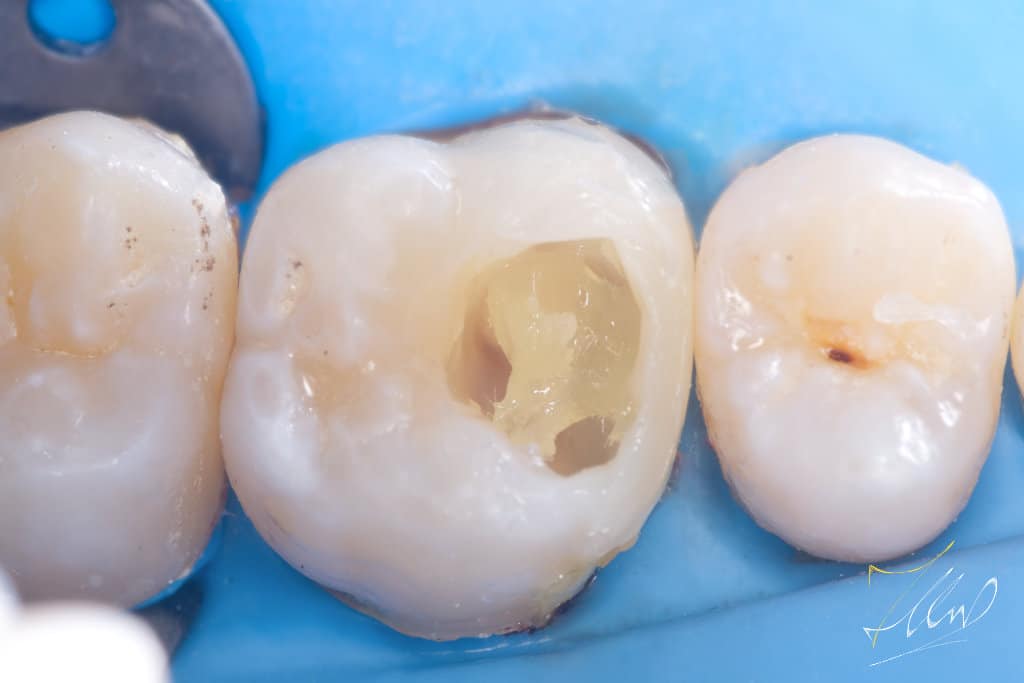

To facilitate matrix placement and achieve optimal contact and contour, it is essential to restore the buccal wall to its original shape.By marking the lost structure and build the buccal cusp to enhance the structure, consider reinforcing the buccal cusp with composite material and then inserting FRC (ever x) to effectively manage the separation force of the ring without compromising the integrity of the composite.